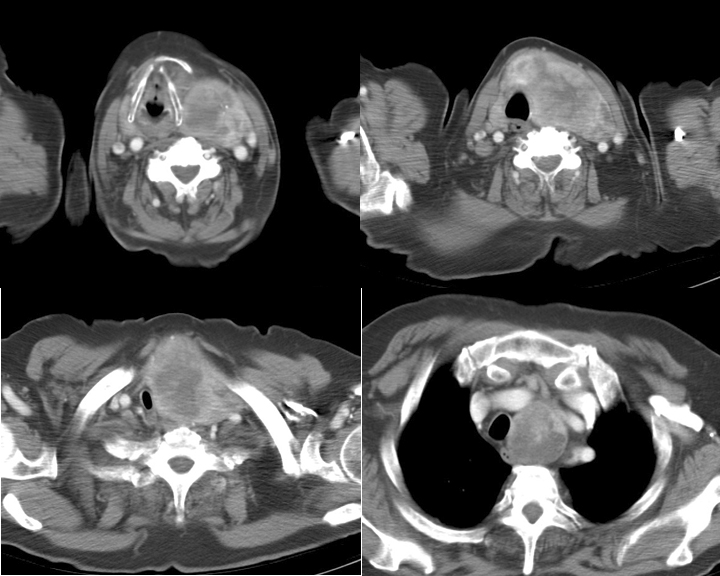

Thyroid Mass

Case 10 CT